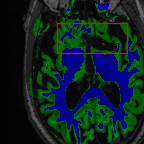

Sparsity LI 2D CNN 3D CNN Ours GT

4 Refer to caption (a) 0.6787/0.7972 Refer to caption (b) 0.8143/0.8776 Refer to caption (c) 0.8190/0.8714 Refer to caption (d) 0.8664/0.9085 Refer to caption (e) GM/WM

Refer to caption (f) 0.6808/0.7161 Refer to caption (g) 0.8103/0.8631 Refer to caption (h) 0.7950/0.8606 Refer to caption (i) 0.8598/0.9115 Refer to caption (j) GM/WM

8 Refer to caption (k) 0.5139/0.7240 Refer to caption (l) 0.6619/0.8224 Refer to caption (m) 0.6878/0.8584 Refer to caption (n) 0.7798/0.8853 Refer to caption (o) GM/WM

Refer to caption (p) 0.5910/0.6947 Refer to caption (q) 0.6516/0.8021 Refer to caption (r) 0.6507/0.8186 Refer to caption (s) 0.7471/0.8540 Refer to caption (t) GM/WM

Figure 6: Visual comparison of gray matter (Green)/white matter (Blue) segmentation over different methods, with respective DICE scores listed under the images.

In Fig. 6, we demonstrate the advantage of the proposed method in brain matter segmentation. It is clear that although 2D and 3D CNN generates visually plausible interpolation as presented in Fig. 5, the brain matters are easily misclassified due to incorrect anatomical structures and blurred details.